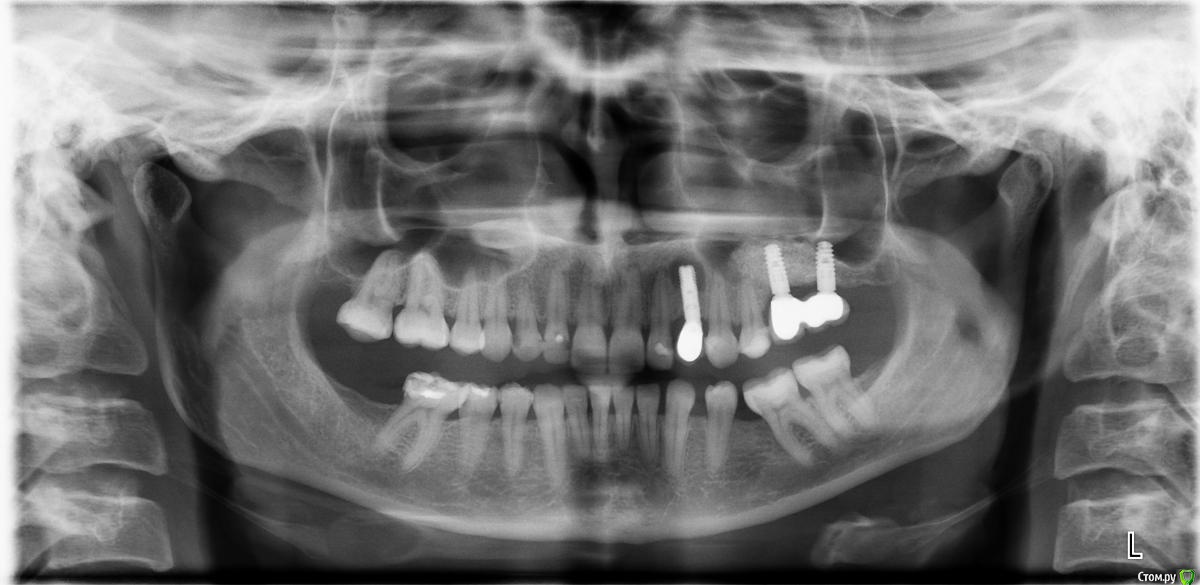

Ю.Ягн Опубликовано 30 марта, 2018 Поделиться Опубликовано 30 марта, 2018 (изменено) Добрый день!Спустя три года после имплантации, начался насморк и заложенность одной ноздри при выявлении причин насморка сделали снимок.Если нужно есть ещё КТ.Очень хочется понять отчего могло такое произойти, ведь есть ещё 2 импланта Изменено 30 марта, 2018 пользователем Ю.Ягн Ссылка на комментарий

Ю.Ягн Опубликовано 30 марта, 2018 Автор Поделиться Опубликовано 30 марта, 2018 (изменено) Имплантолог предполагал, что инфекция пошла от двойки, но связи не было обнаружено.Мне 30 лет2ое детейработаникаких серьезных хронических заболеванийВ декабре болела ангиной (очень тяжело - 2 курса антибиотиков), а феврале ОРВИ. тоже тяжело 6 дней т. 39. 5 потом бронхит и антибиотики.Стала чихать более сказать нечего. Имплантант ставили сразу после удаления шатающегося молочного зуба в 15 году, сейчас имплантант неподвиженКТкт 24.03.2018 юля орто.7z http://fayloobmennik.cloud/7235123 Изменено 30 марта, 2018 пользователем Ю.Ягн Ссылка на комментарий

колесников Опубликовано 31 марта, 2018 Поделиться Опубликовано 31 марта, 2018 Возможно просто длинный имплант,надо кт посмотреть Ссылка на комментарий

Ю.Ягн Опубликовано 1 апреля, 2018 Автор Поделиться Опубликовано 1 апреля, 2018 (изменено) Меня уже прооперировали, подняли дену вычистили размягченную кость, за имплант было не зайти, поэтому разрезали небо, вычистили там, имплант и после этого был абсолютно неподвижен, положили "специальную белую тряпочку" зашили небо, со стороны губы насыпали Био Ос, на снимке после кость стала выглядеть идеально))) Теперь ждемссс.... Но врач не может сказать почему так случилось, что со стороны десны все идеально, пазухи чистые, вариант что три года назад занесли инфекцию во время имплантации и только сейчас она проявилась - практически невероятен, никакой связи с двойкой тоже не увидели. Поэтому я предполагала, что вы сможете предположить варианты, а я их скажу врачу и вместе подумаем, правда он мне уже рекомендовал обратиться к терапевту и провести диспансеризацию ))) У меня этот имплант фирмы Ankylos, а дальние Astra Tesh, беспокоюсь, вдруг у меня непереносимость - аллергия именно на этот имплант и все муки которые я сейчас переношу будут впустую... Изменено 1 апреля, 2018 пользователем Ю.Ягн Ссылка на комментарий

Bier Опубликовано 2 апреля, 2018 Поделиться Опубликовано 2 апреля, 2018 Эта проблема там давно, возникла еще при установке, другим имплантатам не страшно. До конца этиология таких процессов не раскрыта. Возможно перегрев кости или ее излишнее сдавление во время установки. Ссылка на комментарий